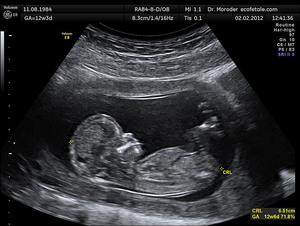

This picture shows an ultrasound image of a foetus inside a uterus.

Ultrasound imaging is a technique that uses ultrasound to form an image of the internal structure of an object.

Ultrasound is used in hospitals to create images of organs and of the foetus of pregnant females.